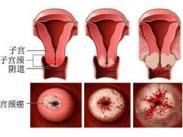

子宫癌

628健康网为您分享有关子宫癌的症状,子宫癌的治疗方法,子宫癌的预防知识,子宫癌的症状图片,子宫癌吃什么药,子宫癌怎么治...